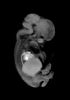

Carnegie Stage 22 (54 post-ovulatory days)

Most embryos at stage 22 are approximately 54 postovulatory days old and measure 25-27 mm in length. Distinguishing criteria for this stage include clear formation of the external ear, the hands begin to extend ventrally beyond the body wall, the fingers of one hand may overlap the fingers of the opposite hand, thickened eyelids just begin to cover the outer margins of the eye, and the superficial vascular plexus of the head now extends about three-quarters of the way above the eye-ear level.